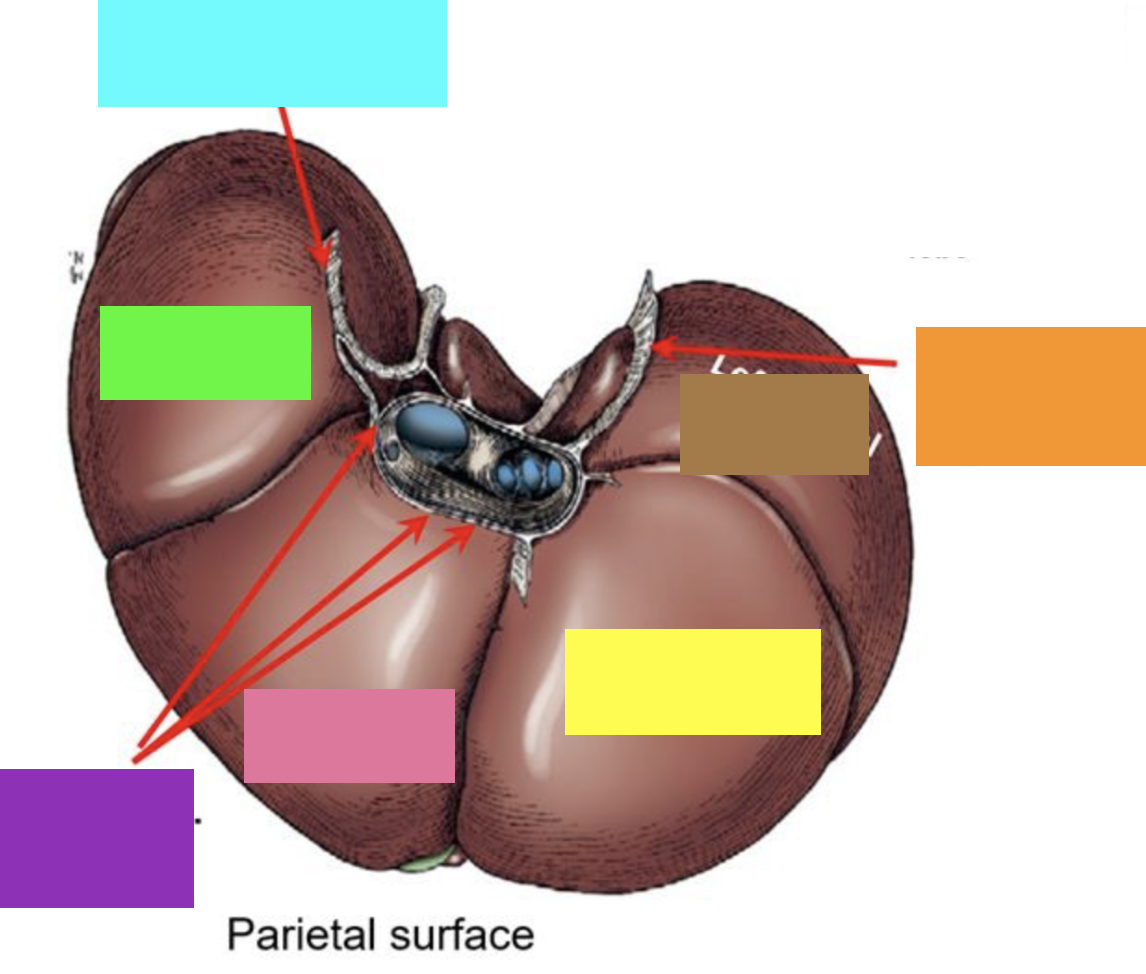

blue box

right triangular ligament

green box

right lateral lobe

purple box

coronary ligament

pink box

right medial lobe

yellow box

left medial lobe

orange box

left triangular ligament

brown box

left lateral lobe